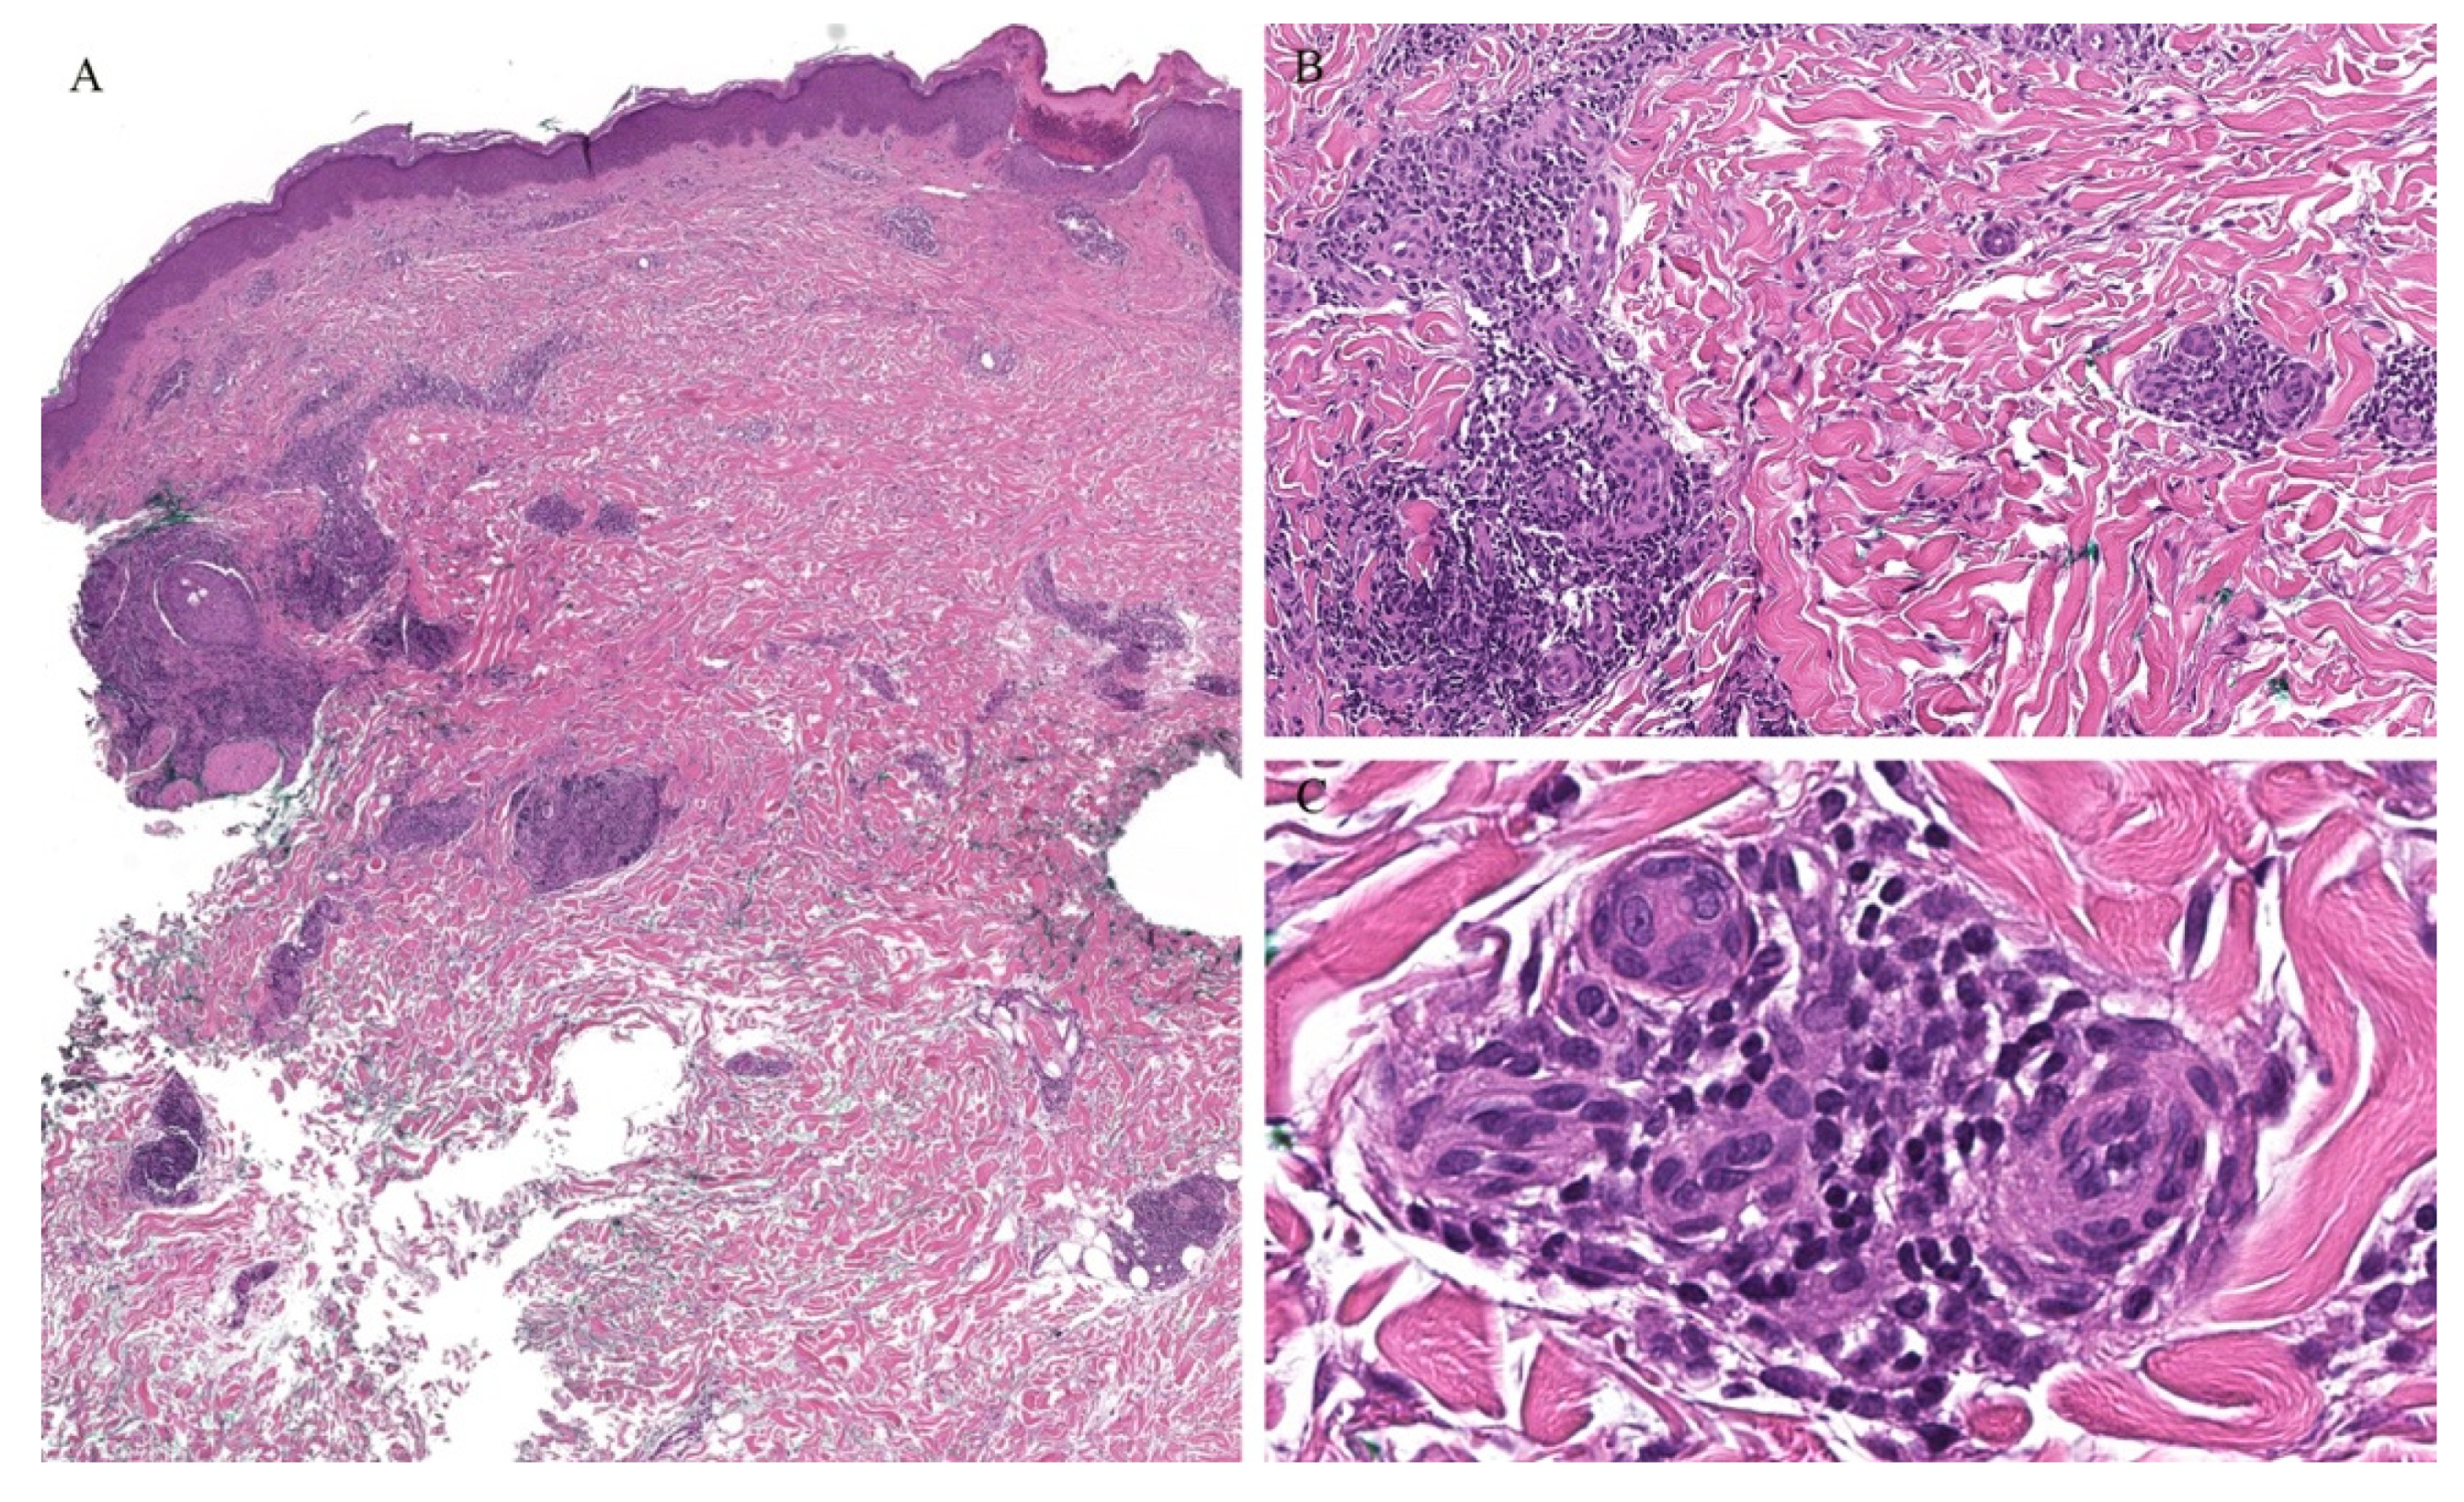

Follicular MF is a variant of MF whereby the atypical lymphocytes infiltrate the hair follicle (Figure 10). Clinically, this condition is mainly seen over the head and neck areas and may be associated with alopecia.

Figure 10.

(A–C) Histopathology of follicular mycosis fungoides.

Histopathologically, follicular MF is usually characterized by a mildly atypical, variably pleomorphic lymphocytic infiltrate with perifollicular accentuation with associated cysts in up to 36% of cases. The epidermis is commonly spared. Mucin deposits in the follicular epithelium (follicular mucinosis) characterizes FMF and has been described in around 75% of cases. In addition, concomitant perieccrine infiltrates have been reported in 4% to 33% of cases. Distinguishing between follicular MF and follicular mucinosis may be challenging, however necessary, as the two entities vary in outcomes and prognosis. In the case of follicular mucinosis, follicular involvement may be observed in the form of mucinous degeneration of the hair follicle [45]. Follicular mucinosis in the absence of mycosis fungoides confers a benign course. However, in follicular MF, intrafollicular mucin deposition secondary to the lymphocytic infiltrate of the follicular epithelium can be observed [46].

Syringotropic MF has also been described with marked eccrine gland and duct epitheliotropism (Figure 11). Clinically, this may appear as a solitary lesion or multiple localized lesions. Alopecia has also been described in syringotropic MF. In addition, syringometaplasia has also been reported in a few cases [47].

Figure 11.

(A–C) Histopathology of syringotropic mycosis fungoides.

Involvement of the hair follicle and eccrine glands have been reported concomitantly within the same biopsy specimens. In one study of patients with folliculotropic MF, eccrine involvement was reported in up to 56% of the cases [46]. In addition, two cases of concomitant folliculotropic and syringotropic MF without any epidermal involvement have been described, illustrating a major pitfall in recognizing MF without the classical features of epidermotropism [48].